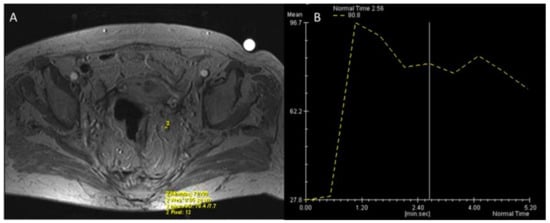

- Petrillo, A.; Fusco, R.; Petrillo, M.; Granata, V.; Bianco, F.; Marzo, M.D.; Delrio, P.; Tatangelo, F.; Botti, G.; Pecori, B.; et al. DCE-MRI Time–Intensity Curve Visual Inspection to Assess Pathological Response after Neoadjuvant Therapy in Locally Advanced Rectal Cancer. Jpn. J. Radiol. 2018, 36, 611–621. [Google Scholar] [CrossRef] [PubMed]

- Alberda, W.J.; Dassen, H.P.N.; Dwarkasing, R.S.; Willemssen, F.E.J.A.; van der Pool, A.E.M.; de Wilt, J.H.W.; Burger, J.W.A.; Verhoef, C. Prediction of Tumor Stage and Lymph Node Involvement with Dynamic Contrast-Enhanced MRI after Chemoradiotherapy for Locally Advanced Rectal Cancer. Int. J. Color. Dis. 2012, 28, 573–580. [Google Scholar] [CrossRef]

- Yu, X.; Wen, L.; Hou, J.; Wang, H.; Lu, Q. Discrimination of Metastatic from Non-Metastatic Mesorectal Lymph Nodes in Rectal Cancer Using Quantitative Dynamic Contrast-Enhanced Magnetic Resonance Imaging. J. Huazhong Univ. Sci. Technol. Med. Sci. 2016, 36, 594–600. [Google Scholar] [CrossRef]